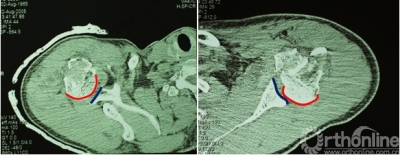

2.肩关节CT

确定肩关节后脱位。

了解反Hill-sachs损伤和程度。

观察肱骨近端主要骨折线和次要骨折线及形态。

Ⅱ型: +肱骨颈骨折+小结节骨折(病例3)。

Ⅲ型: +肱骨颈骨折+小结节骨折+大结节骨折(病例2),以骨折线向肱骨近端外侧壁延伸为另一特征。

五、反Hill-Sachs 损伤对肩关节稳定性的影响

1.反Hill-Sachs损伤范围对肩关节后方稳定性具有决定性的影响。